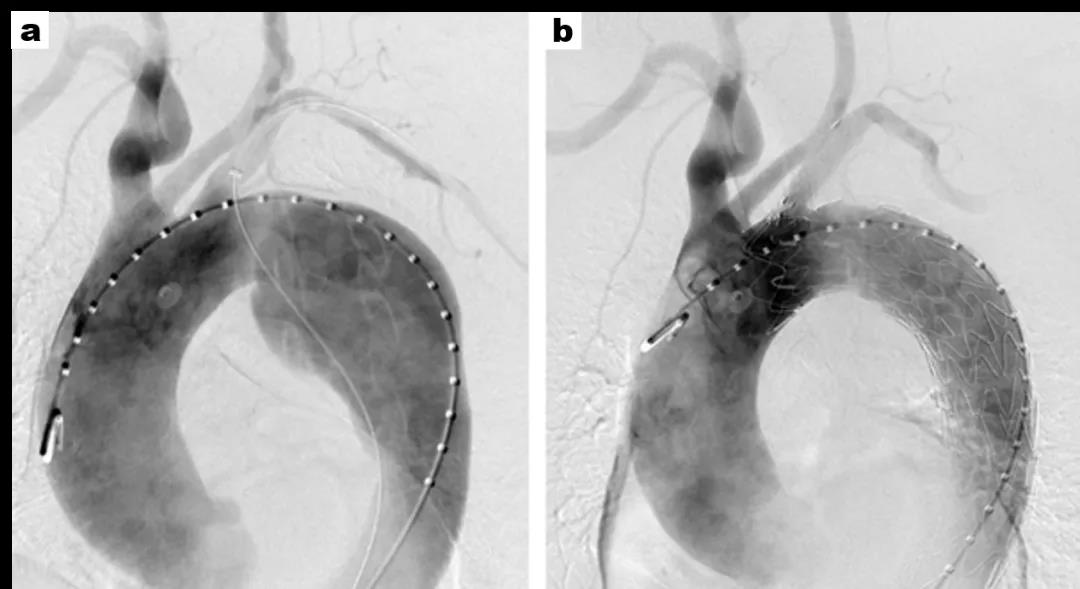

术前(a)夹层动脉瘤明显累及弓部

术后(b)夹层动脉瘤被完全隔绝